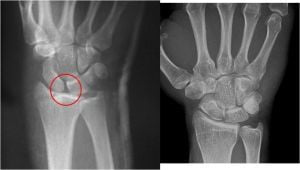

La pérdida de relación entre el escafoides y el semilunar, debida a la rotura de los ligamentos escafolunares, produce un tipo de inestabilidad parecido al de las pseudoartrosis de escafoides, excepto que en este caso es todo el escafoides el que sufre una anormal flexión palmar con subluxación dorsal de su polo proximal. El semilunar, no siendo ya controlado lateralmente por el escafoides, sigue al piramidal hacia una anormal extensión (DISI), a la vez que experimenta un característico desplazamiento en forma de supinación y traslación cubital. Dicho desplazamiento provoca una diástasis, de más de 3 mm del espacio escafolunar (Signo de Terry Thomas), con la consiguiente incongruencia articular radiocarpiana y mediocarpiana.

Los estudios incluyen una vista lateral estricta y vista anteroposterior con la muñeca en posición neutra, desviación radial y cubital. Además deben tomarse radiografías de la muñeca contralateral (comparación entre ambas). Se realiza medición en vista lateral, del ángulo escafolunar (trazar líneas a lo largo de los ejes del escafoides y semilunar). Se considera normal entre los 30º y 60º.